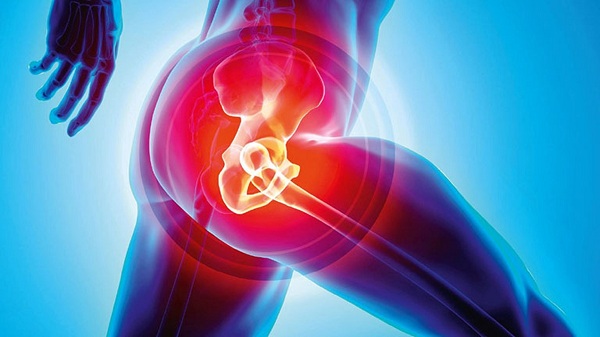

Khớp háng là gì và vì sao dễ bị đau nhức?

Khớp háng là một trong những khớp lớn và quan trọng nhất của cơ thể, đóng vai trò kết nối xương đùi với khung chậu. Đây là khớp chịu lực chính khi đứng, đi, chạy, ngồi xuống hay đứng lên. Chính vì phải hoạt động liên tục và chịu trọng lượng lớn nên khớp háng rất dễ bị tổn thương theo thời gian.

Khi cấu trúc sụn khớp, xương, dây chằng hoặc dịch khớp bị ảnh hưởng, người bệnh sẽ cảm nhận rõ cơn đau nhức tại vùng háng, lan xuống đùi hoặc mông, thậm chí gây hạn chế vận động nghiêm trọng.